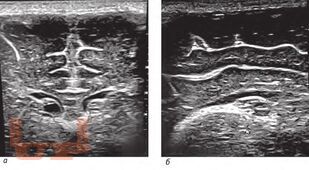

Внутрижелудочковые кровоизлияния у недоношенных новорожденных

В учебном пособии рассматривается проблема персонализации медицинской помощи недоношенным новорожденным с внутрижелудочковыми кровоизлияниями.

Учебное пособие предназначено для неврологов, неонатологов, нейрохирургов, врачей ультразвуковой диагностики и врачей других специальностей, участвующих в оказании медицинской помощи новорожденным с внутрижелудочковыми кровоизлияниями.